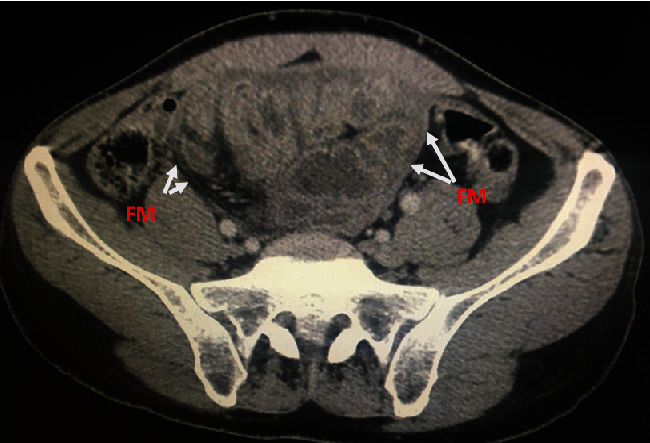

Sclerosing encapsulating peritonitis (SEP) is an unusual fibroinflammatory disease of the peritoneum marked by the development of a fibrous membrane enveloping generally the small intestines. The knowledge around this subject is not completely understood. And the etiology can be either idiopathic or secondary to several diseases, treatments, and/or medications. We present a case of a 52-year-old man suffering from atypical clinical symptoms including recurrent abdominal ascites and intestinal obstruction. An abdominal computed tomography showed findings typical of SEP. Therefore, the patient benefited from exploratory laparotomy, which confirmed the diagnosis of idiopathic SEP. Postoperatively, he again had an episode of bowel obstruction, but this was controlled with steroids. Diagnosis of SEP is a real challenge to surgeons, gastroenterologists, and radiologists. And imagery is very helpful to make the diagnosis. Consequently, it is imperative that all hospital practitioners should distinguish between this lesion and other etiology of acute peritonitis.

Abstract Image